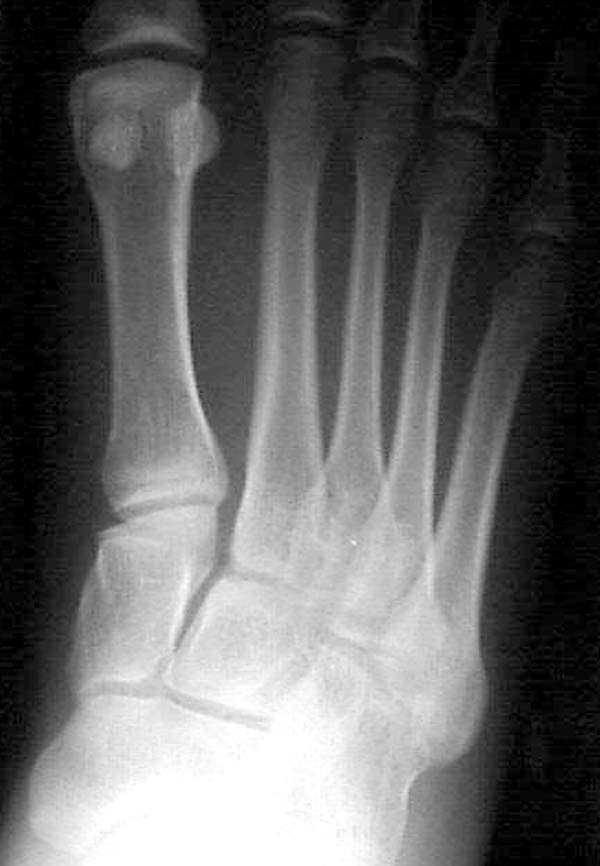

По снимкам нельзя исключить разрыв связки Лисфранка (связки между медиальной клиновидной костью и основанием второй плюсневой). Помогает в диагностике клиника (наличие изолированной гематомы на подошвенной поверхности стопы) и МРТ картина. Если связка повреждена - необходимо оперативное лечение.

по снимкам также нельзя исключить повреждение еще десятка -двух связок. Нормальные снимки.

По первому снимку, не видя больного, мог бы заподозрить перелом основания 3-й плюсневой кости. Поэтому избрал бы тактику консервативного лечения, как при переломе плюсневых костей без смещения!

Здесь КТ и сравнительные снимки стопы под нагрузкой.

Диагностировано повреждение медиальной и латеральной колонны.